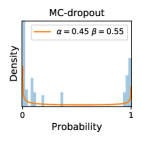

5.1 Distribution of Uncertainty Scores

Distribution of Uncertainty Scores Across Different Severity Levels As explained in Section 3, each uncertainty metric essentially defines an order/ranking among the data points. We conducted an analysis to better understand what data will be assigned high uncertainty under a particular uncertainty metric . Picking out the highest ranked data points (), we calculated the ratio of data points from each SL. Figure 4 summarizes the results as box plots for the Kaggle-DR and the Messidor-2 datasets; additional detailed statistics can be found in Table S.1 in the supplementary materials. From the plot and table, SL1 & SL2 examples account for a higher proportion among the top-ranked uncertain examples across the three ensemble methods. This finding matches our intuition that incipient disease examples (SL1 & SL2) are more likely to be considered uncertain by ensemble methods due to their ambiguity.

Comparing the three ensemble methods in Figure 4, the stacking ensemble method has the highest ratios of SL1 & SL2 data among the high-uncertainty examples it identified under both mean and var. TTA showed slightly better performance than MC-dropout but still falls behind the stacking ensemble method. Considering the fact that SL0 examples accounted for the majority of the dataset, the stacking ensemble method was much more precise (specific) in selecting truly ambiguous data points that were difficult to classify. From Figure 3, we can also see that the stacking ensemble method greatly outperformed the other two methods in finding false negatives under both mean and var uncertainty metrics.

In contrast, the MC-dropout method showed the worst overall performance among the three, as it can be seen from the high ratios of SL0 examples among the uncertain negatives in Figure 4. The histograms in Figure 2 provides another perspective to look into the phenomenon, where a decent proportion of MC-dropout model’s predictions on SL0 inputs entailed low confidence (far from 0 or 1), which from another angle explained why MC-dropout was less specific in terms of lower FNP; many no-DR inputs (i.e. SL0) were erroneously assigned high uncertainty by MC-dropout models.

It is still an open question why the evaluated MC-dropout networks signaled relatively high uncertainty on SL0 & SL3 & SL4 data that are less likely to be ambiguous. We conjecture that much of the “uncertainty” indicated by disagreement among test-time dropout samples actually reflects the stochastic nature of dropout networks rather than the real decision uncertainty associated with the data. It is worth noting that the MC-dropout model we evaluated was not weak per se; they all achieved above Area Under Curve (AUC) scores on test sets. The weakness of individual test-time samples (which explains their low-confidence predictions on SL0 & SL3 & SL4) might have been hidden when they are aggregated into an ensemble—a well-known advantage of ensemble learning. Our results suggested that the uncertainty information given by implicit ensemble methods such as MC-dropout and TTA might not be as reliable as that from explicit ensemble approaches (e.g., stacking ensembles). Similar findings on MC-dropout can be found in some previous papers [1].

As discussed in Section 5.1 and Section 5.3 in the main paper, the mean metric and the stacking ensemble will have better performance in the precision (specificity) on the ambiguous data. Here, more detailed results are shown in Figures S.3 & S.6 and Table S.1. Figures S.3 & S.4 show the histograms of the uncertainty score for Kaggle-DR and Messidor-2 datasets that are the in-distribution (i.d.) dataset in our experiment and FigureS.5 & S.6 show the histograms for ImageNet and CIFAR-10 datasets, which is the o.o.d. datasets in our experiment. Each group of histograms contains results from the three evaluated ensemble methods (stacking ensemble, MC-dropout and TTA) and the three uncertainty metrics (mean, var and kl). Additional detailed results not displayed in Figure 4 can be found in Table S.1, which shows the proportion of the data of different SLs varies across different . For comparison, we also included in Table S.1 the results from single learners, and the proportions of data of different SLs (before any selection was made).